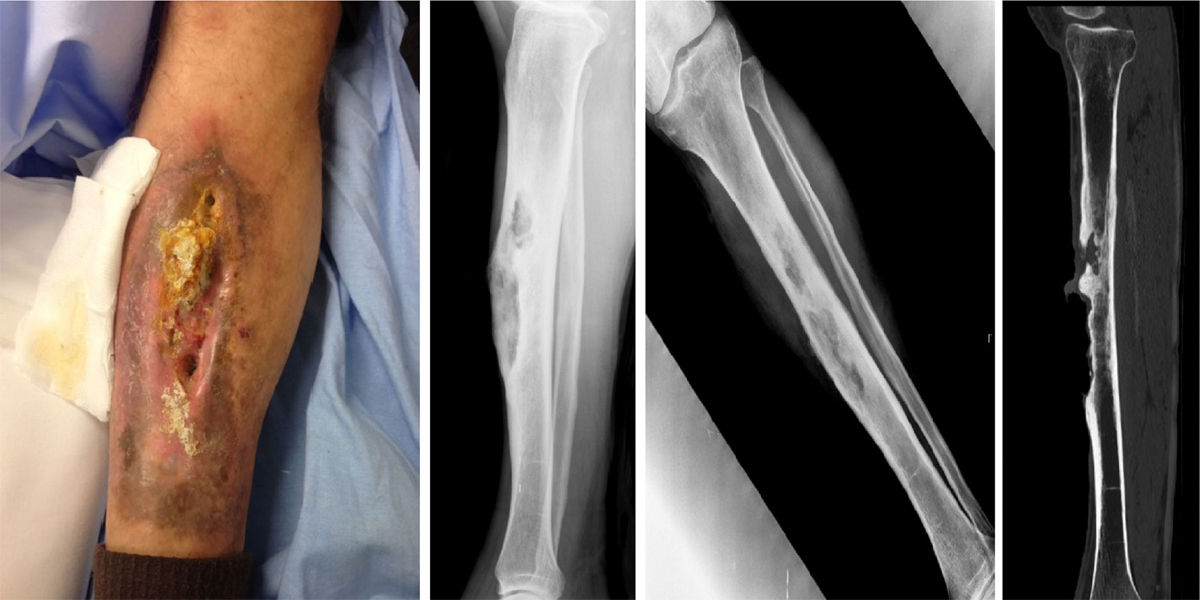

La osteomielitis es una infección ósea caracterizada por la inflamación del hueso y el tejido circundante, provocada generalmente por bacterias.

Los síntomas incluyen dolor en el área afectada, hinchazón, enrojecimiento y calor. Además, los pacientes pueden experimentar fiebre, escalofríos y malestar general. La infección puede afectar la movilidad y la función del hueso afectado, y en casos crónicos, puede causar la formación de abscesos o la destrucción del tejido óseo.

El dolor en el hueso afectado y la fiebre son los síntomas más frecuentes. Es importante conseguir un cultivo de la zona afectada para saber cuál es el microorganismo que produce la infección y administrar así un tratamiento antibiótico dirigido. Otras pruebas diagnósticas que se suelen realizar de forma habitual son la radiografía simple, la tomografía computarizada (TC), o la resonancia magnética nuclear, además de análisis de sangre.